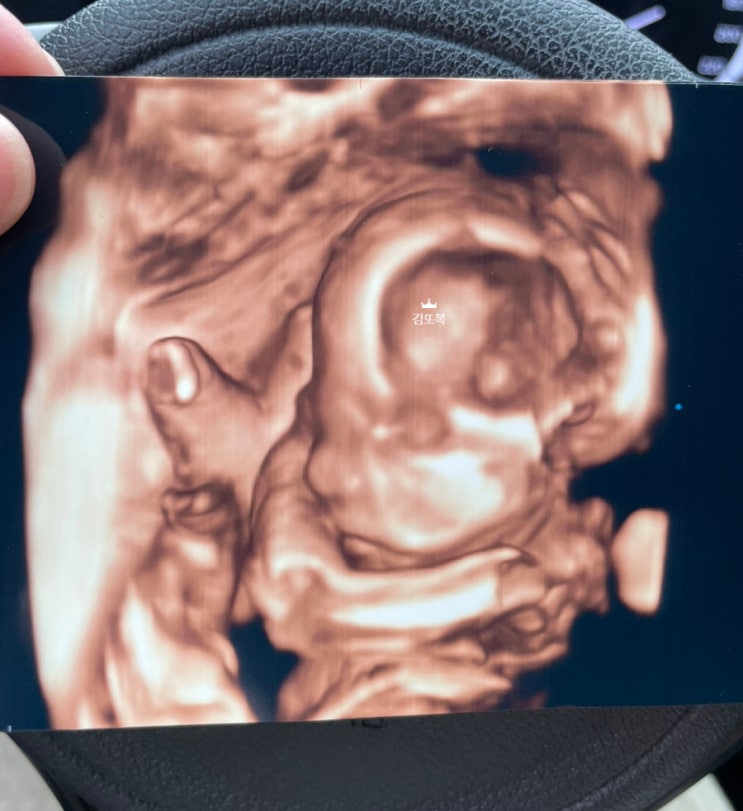

[임신일기 27주~31주] 임신중기, 임신중독증, 만삭사진, 임산부단백뇨, 단백뇨식단, 양수냠냠, 폭풍태동, 바느질태교, 나의일상

23년11월 7일 (29w5d) 만삭사진은 28주에서 32주 사이가 가장 예쁘다고 한닷 마침 병원 가는 날 예약 가능...